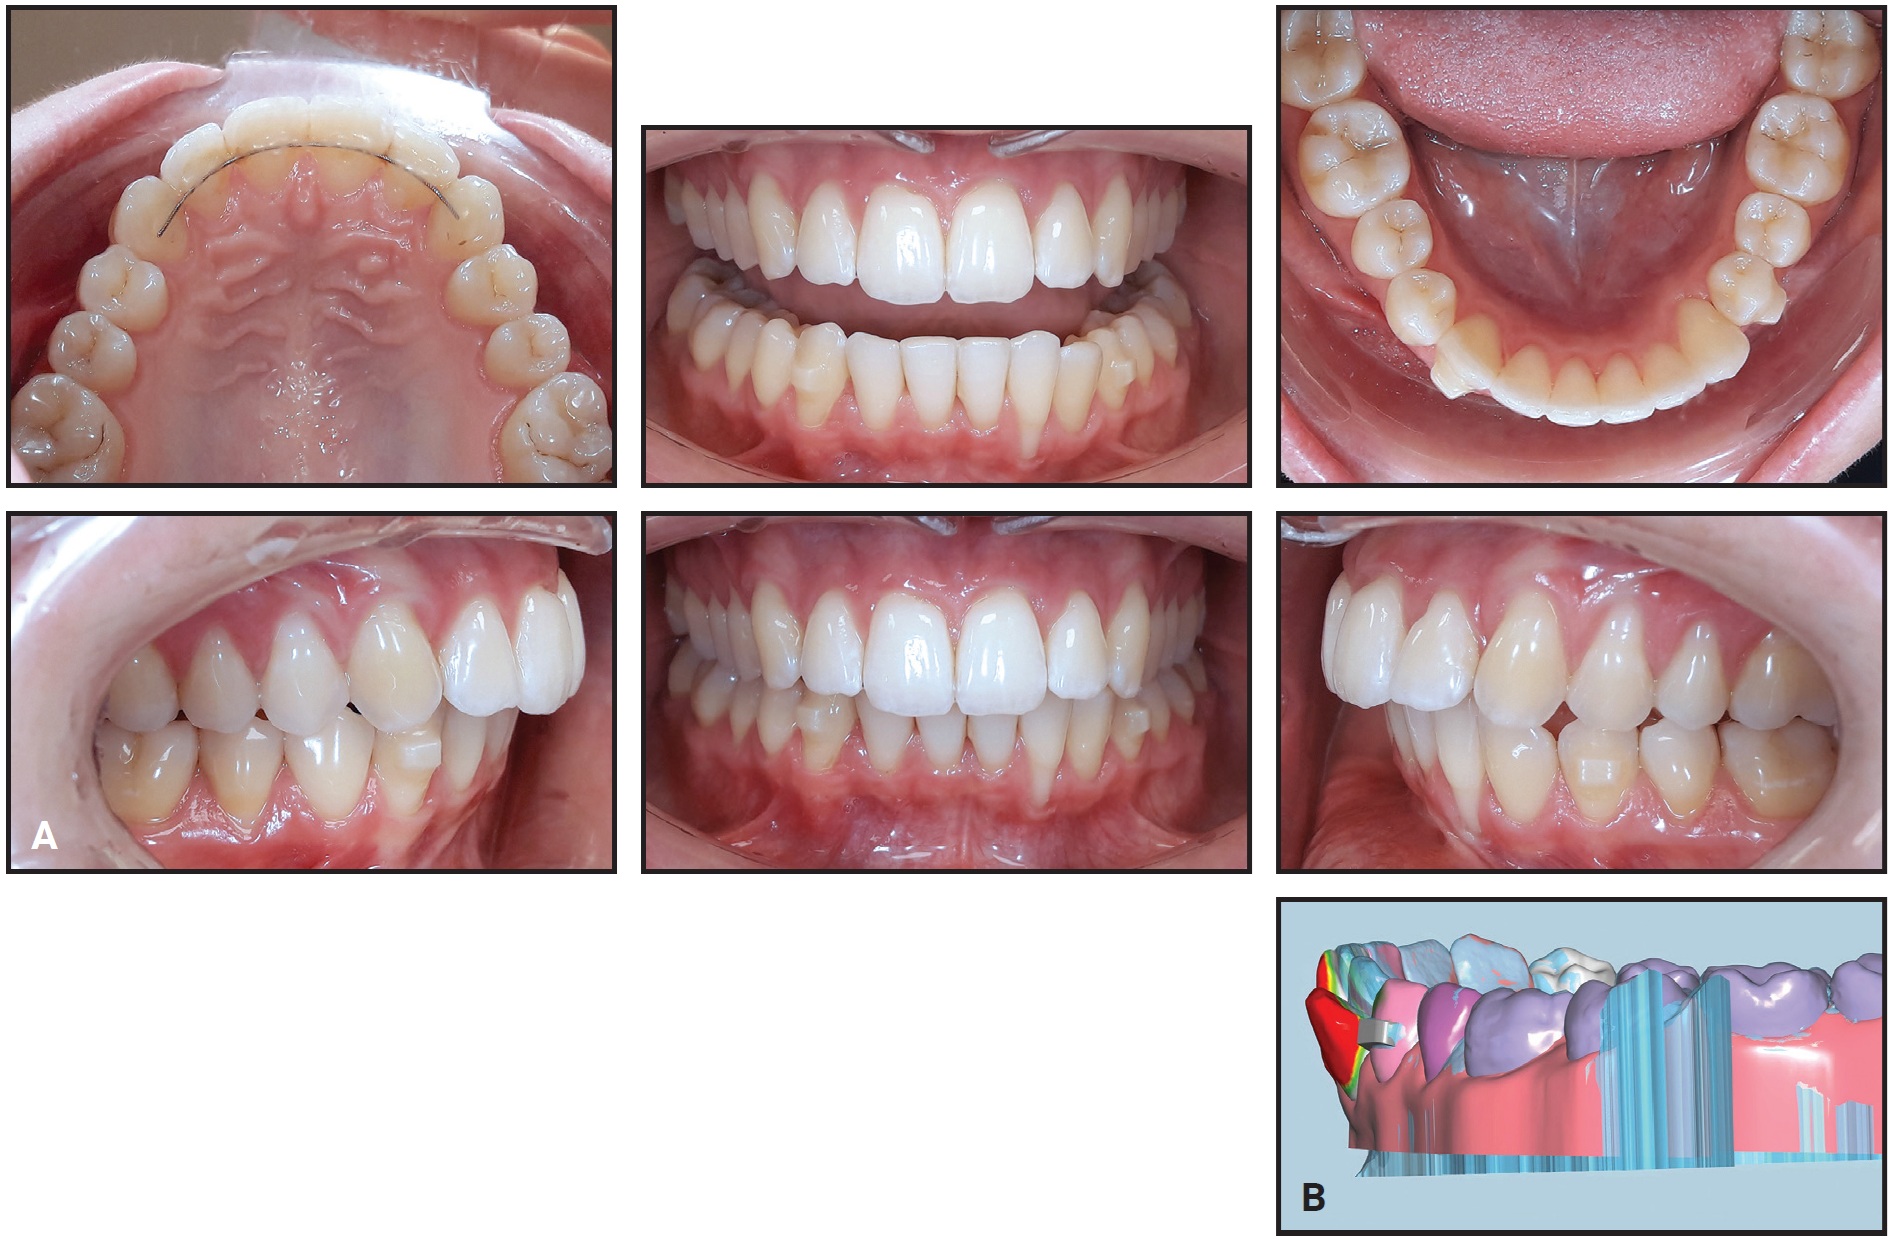

After the first nine steps had aligned the lower left canine and incisors (Fig. 3), six more aligners were produced for an additional three steps of refinement.

Fig. 3 A. After 18 weeks of treatment with 3D-printed aligners. B. Comparison with pretreatment model (red = areas of greatest change).

Active treatment thus involved 12 steps, with a total of 24 lower aligners worn for 24 weeks (Fig. 4).

Fig. 4 After 24 weeks, including nine steps of treatment and three steps of refinement.